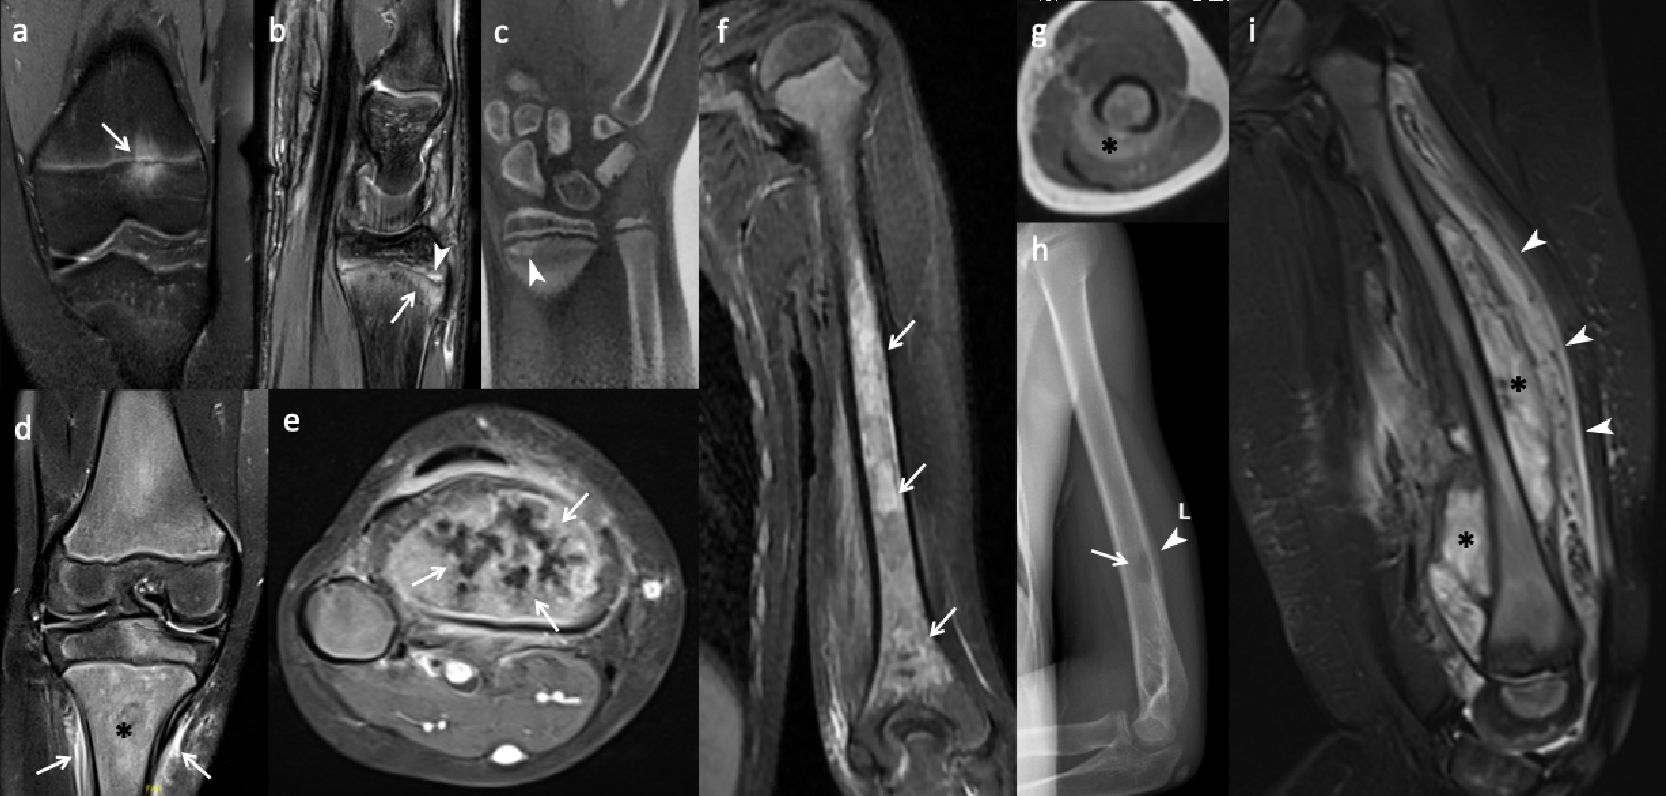

Radiographs and CT reveal round or ovoid osteolytic bone lesions centered at physeal lines which extend to both epiphysis and metaphysis of long bones (Fig. 3a). Sclerotic changes develop subsequently, progressing to hyperostosis and bony expansion, accompanied by a smooth or lamellated periosteal reaction in persistent chronic lesions (Fig. 3b). However, radiographic findings may be occult or normal at the early or healing phases of the disease.11,33

In addition to the initial work-up, radiographs are essential for follow-up of complications. Due to physitis, early physeal closure may occur through the formation of a physeal bridge or bar. Radiographs can demonstrate the characteristic “physeal tongue,” which appears as a lytic or sclerotic tubular structure extending toward the metaphysis. Another point in follow-up imaging is treatment associated findings in patients who were treated with cyclic bisphosphonates (e.g., pamidronate), including fine sclerotic lines in the metaphysis known as zebra stripes, resulting from inhibited osteoclast activity.39

Magnetic resonance imaging

Whether focused or encompassing the whole body, CNO presents several unique characteristics on MRI. The hallmark of CNO on MRI is physitis related periphyseal osteitis that appears as hyperintense foci on fluid sensitive sequences (STIR or T2-weighted fat-saturated) and hypointense foci on T1-weighted images (Fig. 3c). Periosteal reaction, surrounding soft tissue edema and reactive synovitis may accompany the osteitis (Fig. 3d).54 Lesions more commonly locate at the metaphysis or epi-/apophysis of a long bone (Fig. 3c). Diaphyseal involvement is less common (Fig. 3e). In flat and round bones, lesions affect the epi- or metaphyseal-equivalent regions of each bone that are in close proximity to the growth plates (i.e., apophyses of the iliac bones, endplates of the vertebrae, bones surrounding sacroiliac joints, Y-cartilage, ischiopubic synchondrosis) (Fig. 3f, 3g).11,54 Pelvic bones including the proximal femurs and sacroiliac joints are the most commonly involved regions across the body. Long bones of the lower extremity (lower legs and feet > bones around the knee), upper extremities, and vertebral bodies are other sites that are usually involved in descending order. The clavicle, sternum, scapula, and mandible are other involved body parts (Fig. 3h).39 In the spine, the thoracic and sacral vertebrae are the most commonly involved sites and osteitis is usually located focally at the superior endplate of the vertebra.39,55 More importantly, the spine is the commonest site of pathological fracture in CNO and as high as half of cases with spinal disease resulted in vertebral deformities such as vertebra plana or scoliosis (Fig. 3f). 33

After treatment, osteitis foci may fully resolve or heal with sclerosis. Vertebral height loss may persist without osteitis as a marker of previous disease. A diagnostic pitfall after bisphosphonate treatment is the presence of bilateral symmetric bright metaphyseal bands on STIR. These high-signal bands can mimic disease relapse, and their abrupt demarcation in relation to the adjacent metadiaphysis can be a key feature for differentiating them from true osteitis (Fig. 3i).54

CNO mimickers

Normal variants of bone marrow, such as red marrow in the metaphysis during childhood and residual red bone marrow foci in the feet, should not be misinterpreted as osteitis (Fig. 4d). Focal periphyseal edema (FOPE) is another incidental finding located around the physis during the physeal closure period (Fig. 4a). Bone contusions, physeal stress injuries, stress fractures, or reactions may result in or associated with osteitis, but history of trauma—either acute or chronic—and the location of these lesions can help differentiate them from CNO (Fig. 4b, 4c). Hematogenous osteomyelitis can also mimic osteitis in CNO, but in addition to the patient’s history, physical examination, and laboratory findings, the presence of an abscess inside the bone and surrounding soft tissue, heterogeneous enhancement of bone marrow, and localized disease (as opposed to multifocal lesions) can aid in differentiation between these two entities (Fig. 4d, 4e). Neoplastic, infiltrative, or metastatic bone lesions, such as Ewing sarcoma, Langerhans cell histiocytosis, and leukemia, can pose diagnostic challenges; however, factors such as the patient’s age, the presence of an extraosseous solid soft tissue component of the tumor, abrupt lesion contour, and lesion location and shape are key features to consider when evaluating these pathologies (Fig. 4f‒h). Scurvy, as a metabolic condition, is another mimicker that presents with metaphyseal osteitis. However, subperiosteal hemorrhages are not seen in CNO (Fig. 4i).33,54